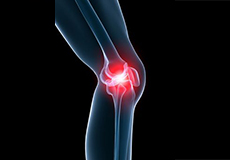

Knee Pain

Knee pain is a common condition affecting individuals of various age groups. It not only affects movement but also impacts your quality of life. An injury or disease of the knee joint or any structure surrounding the knee can result in knee pain. A precise diagnosis of the underlying cause is important to develop an appropriate treatment plan.

Pain, swelling, and stiffness are the common symptoms of any damage or injury to the knee. If care is not taken during the initial phases of injury, it may lead to joint damage, which may end up destroying your knee.